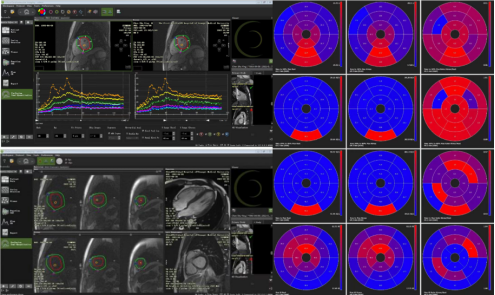

负荷心肌灌注检查增加了心肌微循环障碍患者的检出率,同时我院放射学科可通过后处理软件对微循环障碍进行定量及半定量分析(图2)。负荷心肌灌注可应用于冠状动脉交界性狭窄患者、冠状动脉狭窄<50%的患者以及非缺血性心肌病患者评估其是否存在微循环障碍,是目前检出心肌微循环障碍的可靠且无创的检查方法,可为心内科医生对这类患者进行个性化治疗提供客观依据和疗效评价。